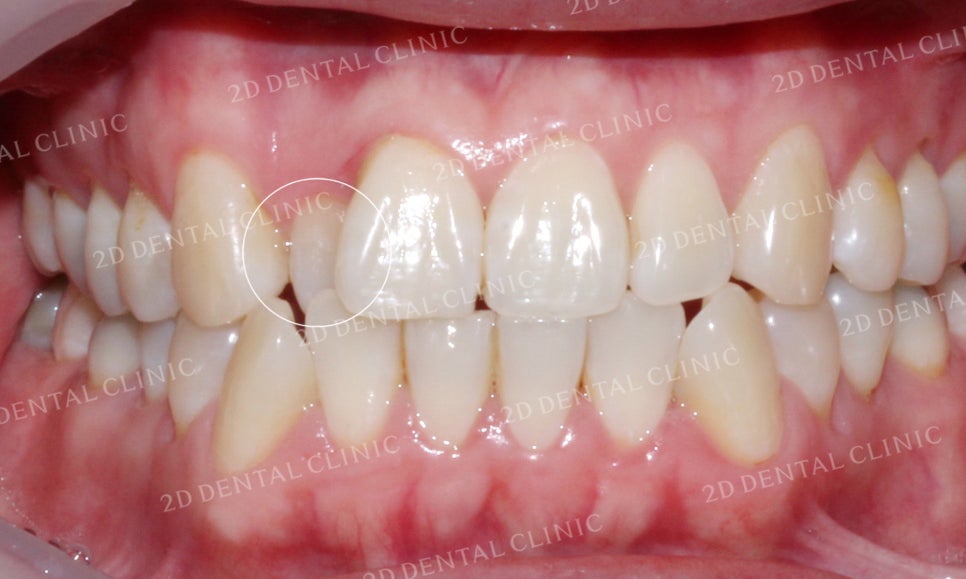

미소 시 심미적으로 거슬리던

12번 치아의 반대교합 증상이

부분교정 후 정상교합으로 바뀐 모습입니다.

<Before> <After>